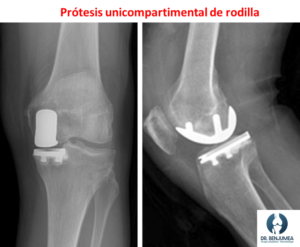

Las prótesis pueden ser completas (Prótesis total de rodilla) o sustituir la mitad enferma de la rodilla (Prótesis unicompartimental de rodilla). Ocasionalmente en personas que padecen lesiones complejas en los ligamentos, habrá que colocar prótesis especiales que nos ayudan a sustituir su función para tener una prótesis estable. Aunque la prótesis de rodilla es una cirugía compleja, los resultados suelen ser muy buenos y los pacientes intervenidos logran eliminar el dolor, recuperar la movilidad y volver a realizar sus actividades de forma normal.

Aunque uno sale andando del hospital, la recuperación completa para hacer una vida sin dolor y poder hacer esfuerzos más importantes se sitúa en unos 3 o 4 meses, aunque los pacientes intervenidos de prótesis unicompartimental suelen recuperarse antes de este tiempo.